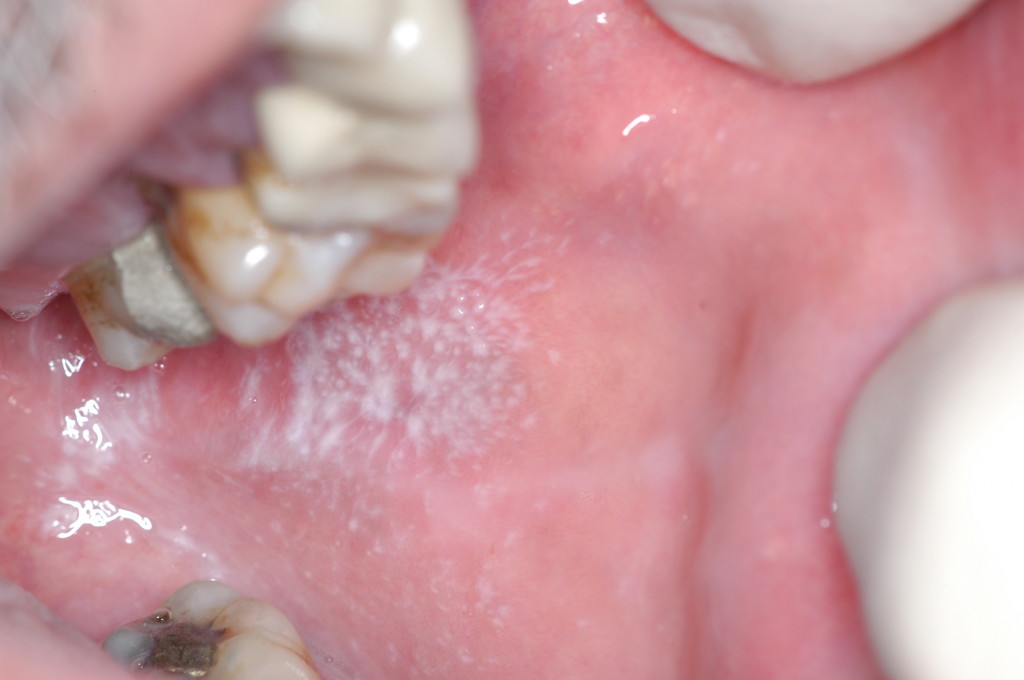

Reticular and erosive oral lichen planus on the buccal mucosa Oral Lichen Planus Reddit Its a lot to manage but you can manage it. Just got diagnosed with erosive oral lichen planus (olp) a couple years ago i (27m) was diagnosed with lichen planus on my genitals by my determalogist. Lichen planus is a chronic inflammatory skin condition. I've been treated for my oral lichen planus with steroids, hydroxychloroquine, methotrexate and now leflunomide. Lichen. Oral Lichen Planus Reddit.

Reticular oral lichen planus affecting the buccal mucosa (Thongprasom Oral Lichen Planus Reddit Lichen planus takes a long time to turn cancerous and less likely if you dont smoke / irritate it with foods and use topical steroids to protect skin. Oral lichen planus is lichen planus inside the mouth. Who gets oral lichen planus? I have done a little searching on reddit and have found a few comments, but nothing recent. Its. Oral Lichen Planus Reddit.